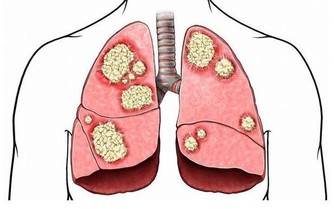

肺對人體的最大貢獻就是供氧氣、排廢氣。這個器官出問題,人體會不能得到足夠的氧,或者累積過多的廢氣廢物。一方面,氧是組織細胞賴以生存和發揮作用的基礎物質,沒有它,臟器罷工,人就不能正常生存。另一方面,廢氣堆積,會進一步損害肺等臟器。護肺養肺非常重要。

要保護肺,有一點很重要,那就是戒菸,以及多呼吸質量好的空氣。保障充足的睡眠也有助於人體對肺的修復。除此之外,飲食對養肺護肺也很重要!

想要肺更好,5種食物可常吃

食物雖然不能治癒疾病,有些卻可以幫助我們潤肺止咳,對緩解哮喘也有很多好處。下面為您介紹5種有助於促進肺健康的食物。